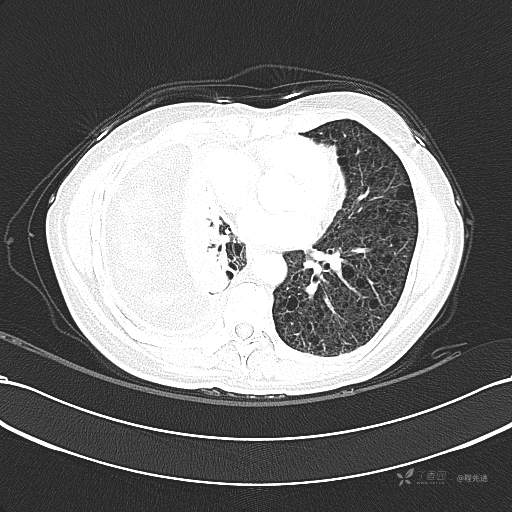

患者性别:女

患者年龄:51岁

简要病史:胸闷半年

肺淋巴管肌瘤病 (7)

乳糜胸 (8)